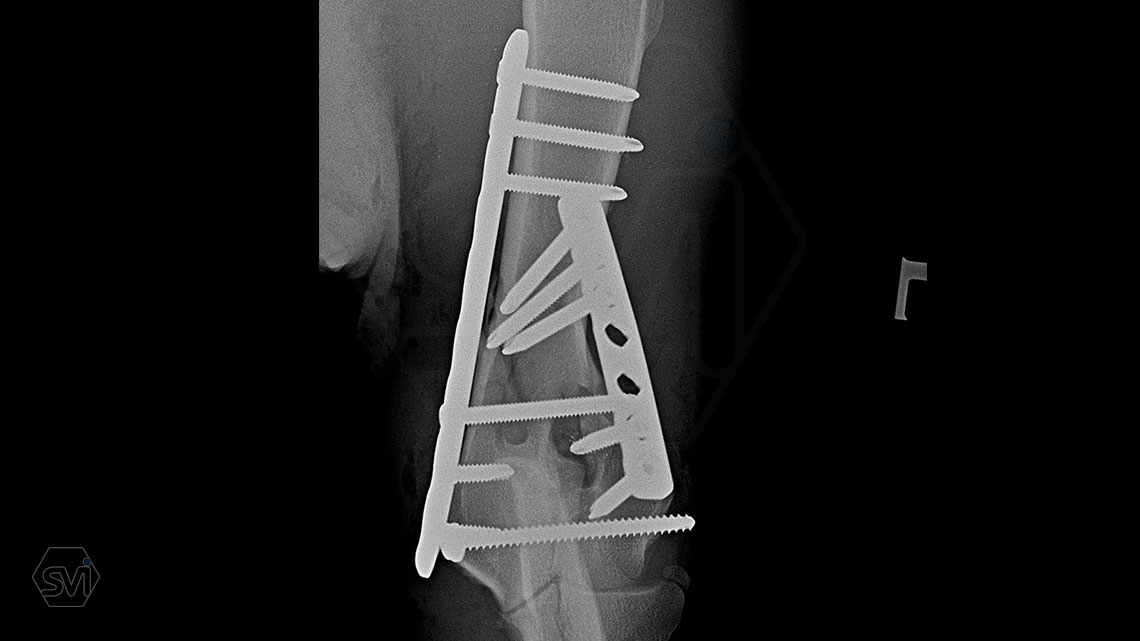

Nightmare for all of us: diastal humeral Y-fracture in a large active dog (German Shepherd)

The damaged area was exposed laterally and medially, and 2 locking plate were used: a large polyiaxial straight plate made with 3.5 mm screws, and a small polyaxial plate laterally with 2.7 mm screws.

The intercondylar fragments were fixed with 3.5mm lag screw with a washer under the head.

The dog was already using his leg very nicely at control 1 month post op., barely limping. In such a case, the advantages of locking systems (distal short screws are also permanently fastened) and polyaxiality (positioning the screws of the opposing plates so that they do not interfere with each other, and avoiding the screw insertion into the joint or fracture line) are really very helpfull.